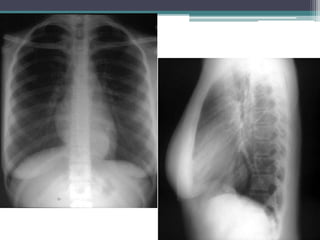

Eighteen year old female

with an incidentally noted

chest mass

Esophageal duplication cyst